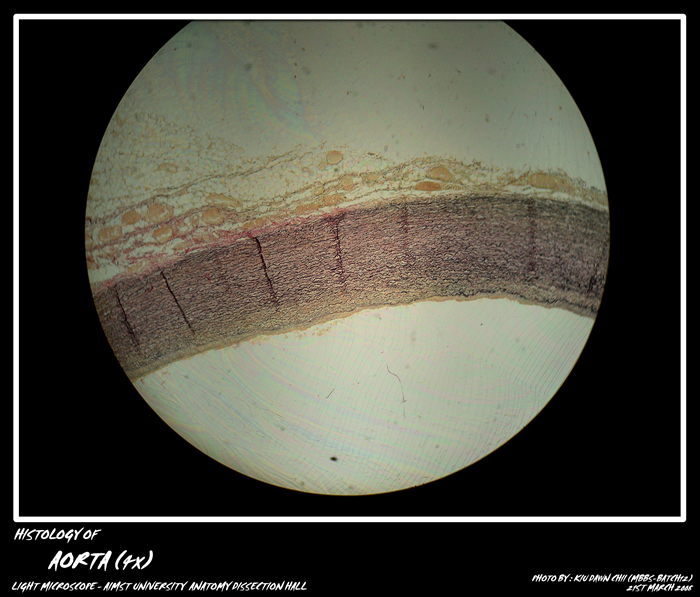

MBBS Batch 12 Histology MicroPhoto Archive

BLOOD VESSEL